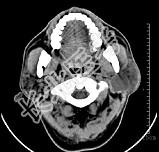

- 多项选择题男性50岁,涕中带血半年, 体检发现左侧颈部多个硬结,CT扫描如图所示, 请选择正确的描述和结论 ( )

A、左侧筛窦内见软组织块影,边缘不规则

B、软组织影累及对侧筛窦、左侧上颌窦

C、左侧眶内壁、上颌窦壁及颅底骨质破坏

D、考虑为左侧筛窦黏液性囊肿

E、考虑为左侧筛窦癌